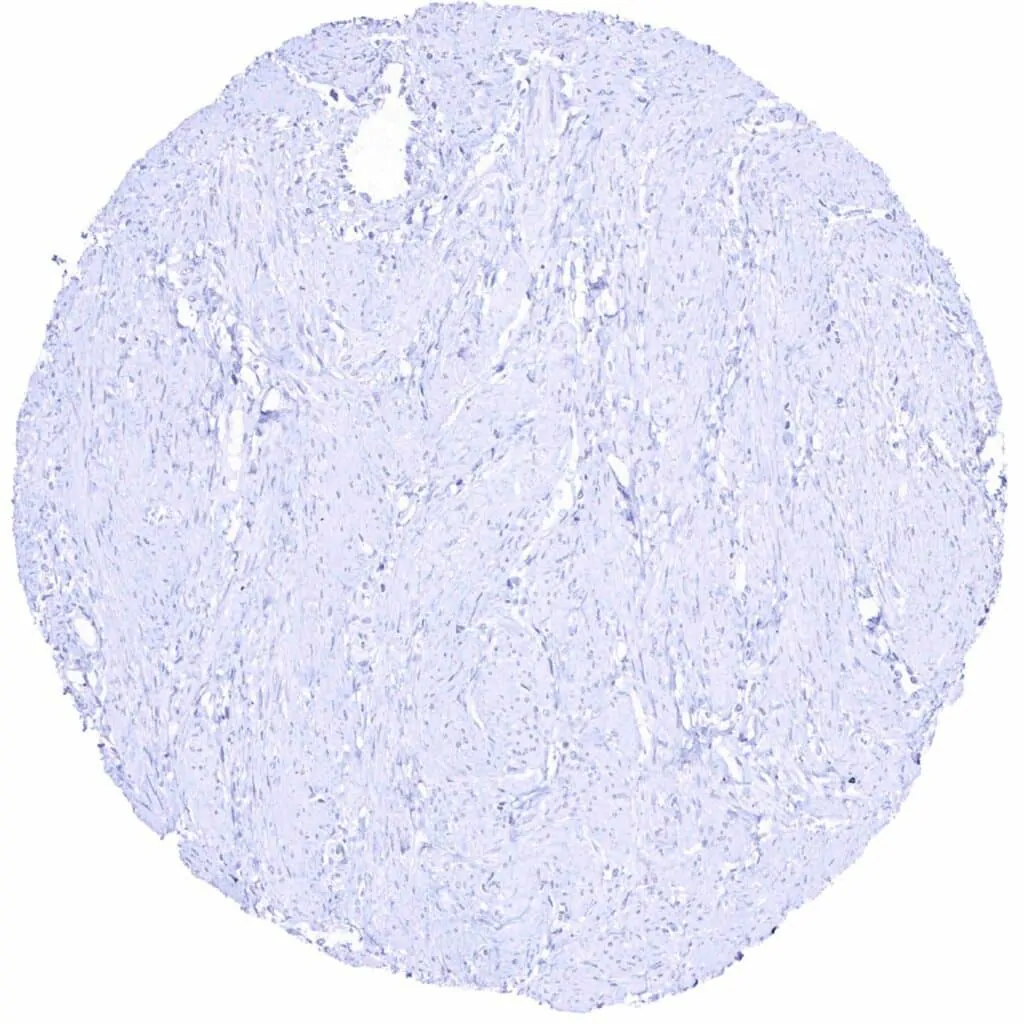

Aorta, media